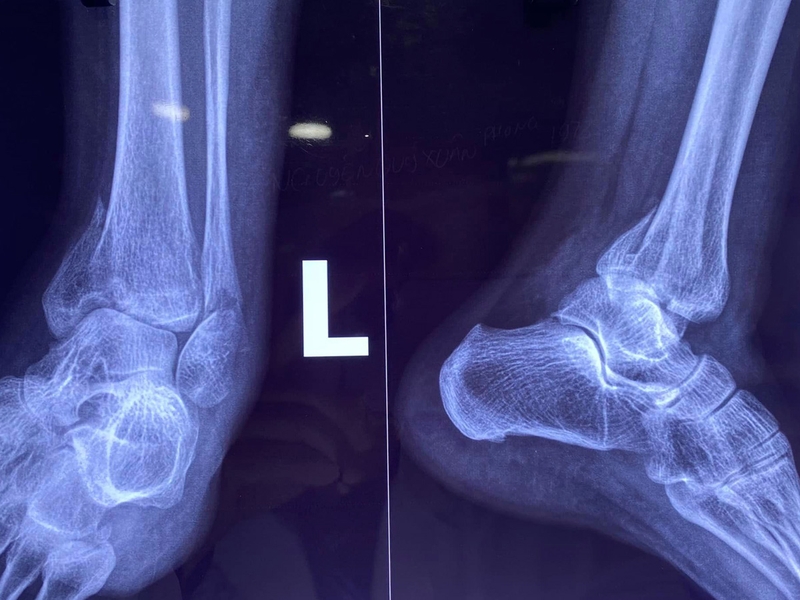

Để chẩn đoán và định hướng điều trị, bác sĩ thường sẽ yêu cầu các kỹ thuật hình ảnh như chụp X-quang, CT-scan, MRI,... Trong số đó, chụp X-quang thường được sử dụng phổ biến nhất vì tính đơn giản và chi phí thấp. Nó giúp bác sĩ xác định vị trí rạn của xương, từ đó đưa ra phương hướng điều trị phù hợp.

Trong trường hợp nứt xương không phức tạp, bác sĩ thường áp dụng các phương pháp điều trị không cần phẫu thuật như bó bột hoặc nẹp cố định chân. Bệnh nhân thường được khuyến khích giữ cố định hoặc hạn chế vận động trong một thời gian nhất định, sau đó sẽ được tái khám theo lịch hẹn. Để đảm bảo việc liền xương, bác sĩ thường sẽ yêu cầu chụp X-quang để kiểm tra sự tiến triển.

Chụp X-quang giúp bác sĩ xác định chính xác vị trí rạn của xương, từ đó đưa ra phương hướng điều trị phù hợp